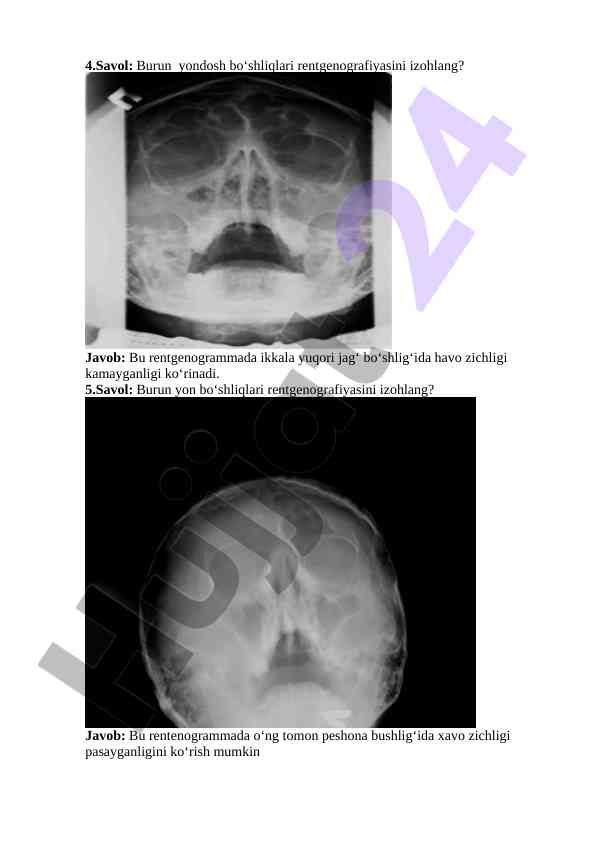

Rentgenografiya bo‘yicha savollar va javoblar, burun yon va ko‘krak qafasining rentgenogrammalarini tahlil qilish. O‘quv jarayoni uchun zarur ma'lumotlar va tahlil mezonlari.